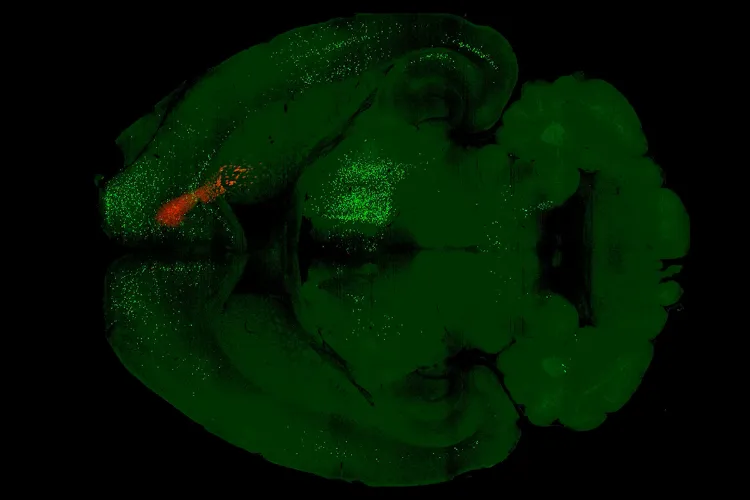

由康奈尔大学生物医学工程学教授Alex Kwan领导的团队,通过对小鼠的研究,首次清晰地描绘出单次剂量的裸盖菇素(Psilocybin,致幻蘑菇中的活性成分)如何对大脑皮层进行“重新布线”。他们的发现,为致幻剂的抗抑郁机制提供了迄今为止最具体的细胞和回路层面的证据。

研究聚焦于小鼠的前额叶皮层(dmPFC),这是大脑中负责高级认知和情绪调节的关键区域,也是裸盖菇素靶点——血清素2A(5-HT2A)受体密集分布的枢纽。利用病毒示踪技术和3D大脑图谱,研究团队得以在微观层面追踪神经元之间的连接变化。